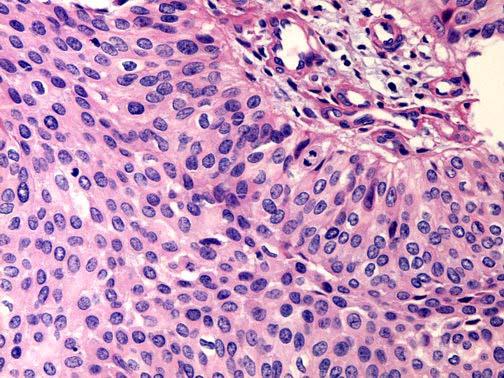

问题 男性,78岁,血尿2年。CT示右侧肾盂内可见软组织密度影,肾盂肾盏受压变形,考虑为肾脏肿瘤,遂行右肾切除,肾脏大体如图所示,镜检如图所示,请做出诊断 ( )

选项 A.右肾透明细胞癌Ⅰ级 B.右肾透明细胞癌Ⅱ级 C.右肾盂移行细胞癌Ⅰ级 D.右肾盂移行细胞癌Ⅱ级 E.右肾盂移行细胞癌Ⅲ级

答案 D